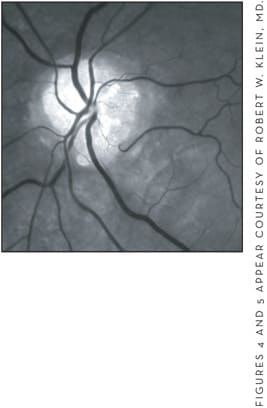

Optic nerve drusen have been described as globular, often calcified, hyaline bodies, in the prelaminar or non-myelinated portions of the optic nerve (Figures 4 and 5). Muller was the first who described histopathologically optic nerve drusen in 1858.13 Histologically, optic nerve drusen are predominantly composed of mucopolysaccharide; calcium and iron have also been demonstrated in drusen.

Figure 4. In this color photograph, the optic nerve drusen appear as globular, yellowish nodules on the surface of the optic disc (left).

Figure 5. The optic drusen are visible on the surface of the optic disc in this red-free photograph (right).